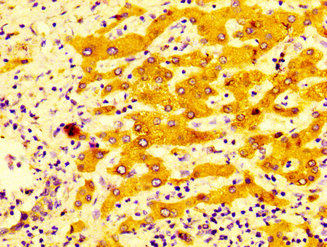

• IHC image of CSB-PA006417LA01HU diluted at 1:400 and staining in paraffin-embedded human liver cancer performed on a Leica BondTM system. After dewaxing and hydration, antigen retrieval was mediated by high pressure in a citrate buffer (pH 6.0). Section was blocked with 10% normal goat serum 30min at RT. Then primary antibody (1% BSA) was incubated at 4°C overnight. The primary is detected by a biotinylated secondary antibody and visualized using an HRP conjugated SP system.